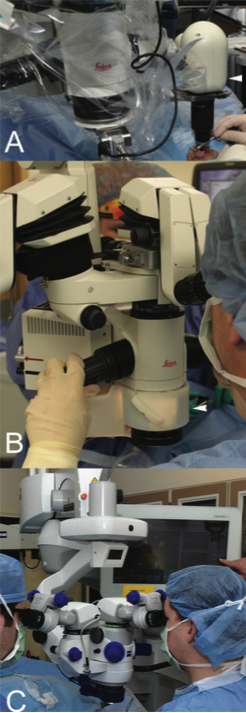

Until recently, the two most common systems described for intraoperative use are the handheld Envisu Spectral Domain Ophthalmic Imaging System (SDOIS; Bioptigen) and the stand-mounted iVue (Optovue). Although both systems enable portability, they carry a significant surgeon learning curve, which diminishes their stability and the reproducibility of scan location. This weakness led to the development of portable scan heads tethered to the operating microscope, which enhanced surgeon control of the system via the operating microscope joystick and allowed greater stability (Figure 1).8 Studies involving microscope-mounted OCT systems showed that imaging can be obtained efficiently and with minimal delay in surgical procedures.8 However, more extensive integration, including true microscope integration allowing real-time intraoperative OCT, is needed to ensure widespread adoption.

Figure 1. Examples of intraoperative OCT systems: microscope-mounted EnVisu system (arrowhead, A); Cole Eye Institute’s microscope-integrated intraoperative OCT prototype (arrowhead, B); Carl Zeiss Meditec’s Rescan 700 microscope-integrated intraoperative OCT system (C).

Real-time imaging provides feedback to surgeons to help guide surgical maneuvers via visualization of tissue-instrument interactions. Research groups initially developed novel prototypes and created microscope-integrated OCT systems (Figure 1).9-12 Each of these systems provided a novel approach to microscope-integrated OCT as an add-on system to a conventional microscope. More recently, there have been significant advances in integrative technology, and more seamless commercial systems have been developed that do not alter the overall form of the microscope head (Figure 1).13,14 Each of these systems represents a significant step toward the adoption of OCT into the surgical setting, allowing true real-time intraoperative OCT with visualization of surgical motion.9,15-17